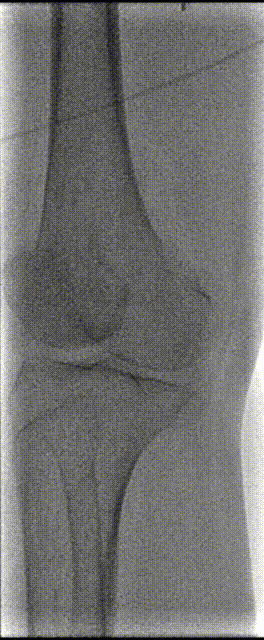

1,患者取平卧位,术区常规消毒、铺单。2%利多卡因局部麻醉满意后,逆行穿刺左侧股总动脉成功后置入血管鞘,经鞘管造影证实在股总动脉,全身肝素化。沿左侧鞘管置入超滑导丝及MPA1导管,导丝、导管配合“翻山”超选进入右髂总动脉,造影见:右髂外动脉、股总动脉、股浅、股深动脉显影良好,腘动脉收肌管部以下及膝下动脉未见显示。

2,保留导丝退出导管及血管鞘,沿导丝置入6F 70cm翻山鞘,置入MPA1导管,超滑导丝、MPA1导管配合通过腘动脉至胫前动脉,经造影证实导管位于真腔。

3. 将导丝更换为Rotarex血栓切除系统导丝,退出MPA1导管,沿导丝导入Rotarex血栓切除导管并连接系统,于腘动脉行血栓旋切抽吸。

4.抽吸后造影见:腘动脉血流恢复,管腔局部可见狭窄,沿导丝导入球囊扩张导管(4*200mm,巴德,6atm,3min)于腘动脉病变内分段扩张。扩张后造影见:右股腘动脉至胫前动脉远端血流恢复。